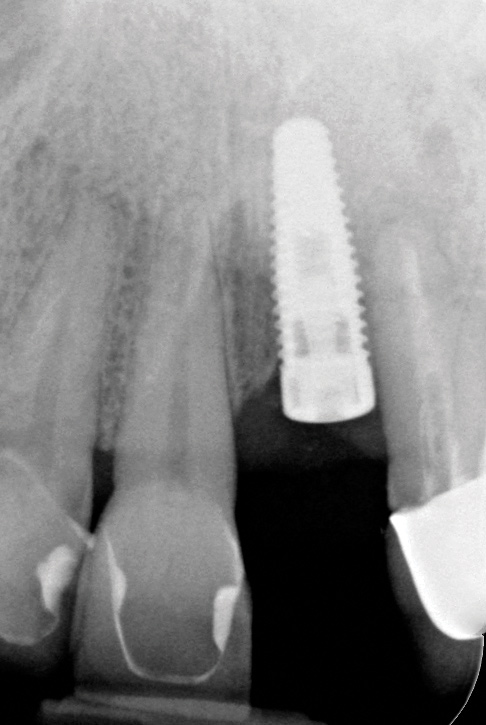

Problem: The implant has bone loss due to peri-implantitis but is not in the esthetic zone and the restoration in place is clinically acceptable. The bone loss has been progressive, and the remaining periodontium is reduced in an area such as a posterior implant (Figure 15 and Figure 16).

Clinical examination showed 2 mm of buccal recession with a shallow vestibule and absence of keratinized attached gingiva against the crown with 8 mm of circumferential pocketing accompanied by bleeding upon probing (Figure 15 and Figure 16). A periapical radiograph showed a symmetrical vertical osseous defect causing the loss of 50% of the bone around the implant (Figure 17). Because the patient had made a significant investment of time and finances to replace her lost tooth with the implant, she desired that the implant and restoration be retained, if feasible.

Fig 17. Radiograph showed symmetrical infrabony defect affecting 50% of the implant surface.

Figure 17